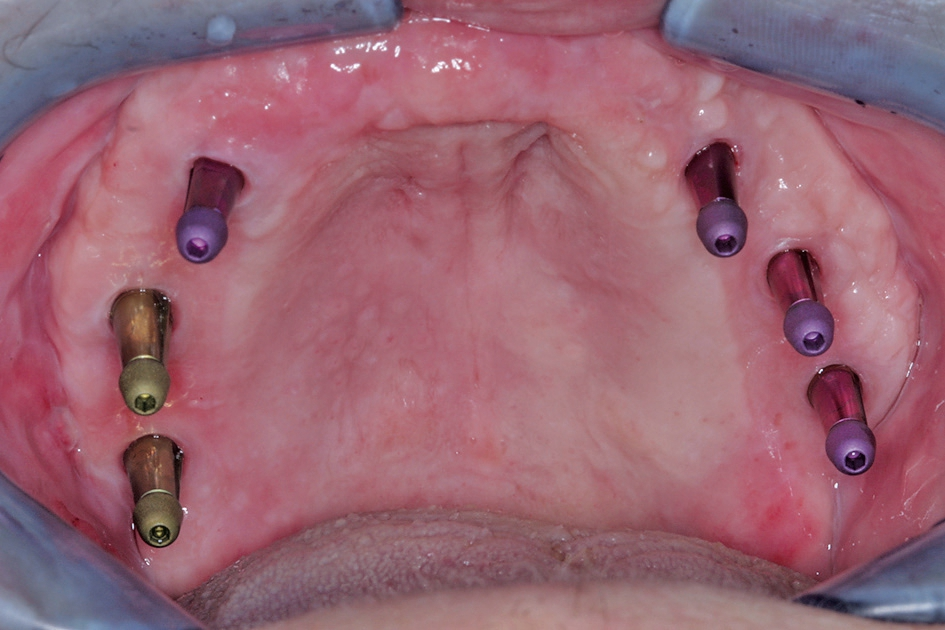

Nach vollständiger Abheilung und Anbringen der Repositions- Übertragungsaufbauten konnten die Implantate im Sinne einer Primärabformung mittels eines konfektionierten Löffels geschlossen abgeformt werden (Abb. 22). Darüber hinaus wurde eine Vorbissnahme genommen, so dass basierend auf diesen Unterlagen im Labor die Sekundärabformung als Pick-Up Abformung vorbereitet werden konnte. Hierzu erfolgte im Labor die Verbindung der Abformpfosten auf dem ersten Arbeitsmodell mit starrem Kunststoffmaterial, welcher in der Folge dann wieder getrennt wurde. Intraoral wurde dieser Trennspalt dann wieder mittels starren Kunststoffmaterials verbunden, so dass eine hohe Präzision der Abformung durch die Versteifung zwischen den Implantatpfeilern gewährleistet werden konnte (Abb. 23). Zudem erfolgte die Herstellung einer verschraubten Bissnahme, welche gerade bei grossspannigen Arbeiten ein späteres Einschleifen der Arbeit erleichtert (Abb. 24). Die Abformung wurde mit einem Polyethermaterial (Impregum, 3M ESPE, Seefeld) ausgeführt, welches sich durch eine sehr gute Formstabilität und gute Rückstellfähigkeit bei kurzer Abbindezeit auszeichnet. Im Labor wurde aus diesen Unterlagen ein Meistermodell mit Gingivamaske hergestellt und eine erste Zahnaufstellung angefertigt.